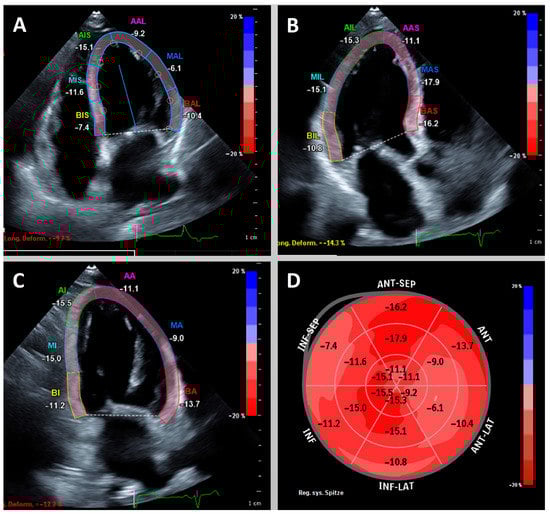

- Schellenberg, J.; Ahathaller, M.; Matits, L.; Kirsten, J.; Kersten, J.; Steinacker, J. Left ventricular global longitudinal strain as a parameter of mild myocardial dysfunction in athletes after COVID-19. Preprint. medRxiv 2023. [Google Scholar] [CrossRef]